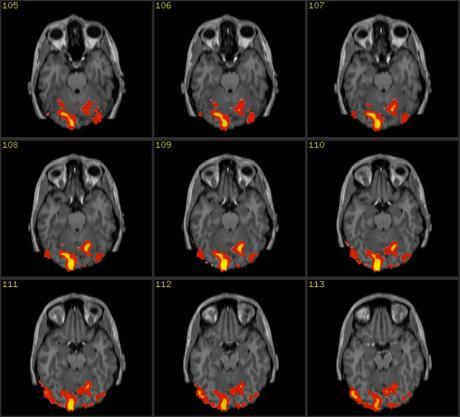

Un grupo de investigadores en la Universidad Carnegie Mellon decidió averiguarlo con un estudio en el que participaron 16 personas. Todas ellas recibieron información sobre ocho animales extintos, incluyendo sus dietas y su hábitat. Andrew Bauer, líder del estudio, y el profesor de neurociencia cognitiva Marcel Just, utilizaron un sistema de resonancia magnética funcional para obtener imágenes precisas mientras todos estos nuevos conceptos eran invocados por el cerebro. Cada uno de esos conceptos generaron una especie de "firma", y con la ayuda de una plataforma de software, los investigadores fueron capaces de reconocer en qué animal estaba pensando cada participante en un momento determinado, lo que podría interpretarse como "leer la mente".